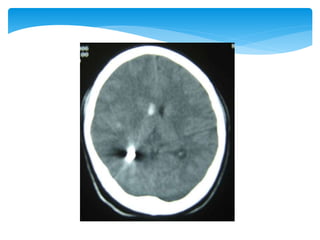

 Appearance of the normal structures

CT Scan

 Appearance ofthe normal structures CT Scan